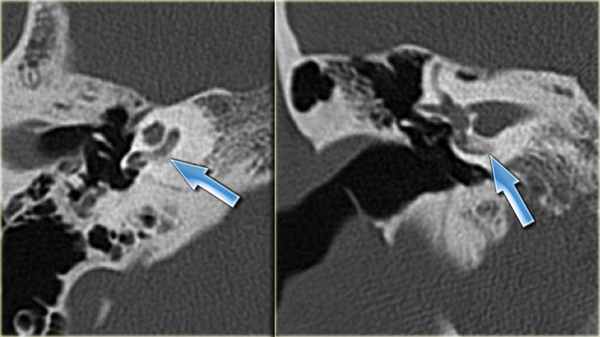

КТ-картина оссификации (обызвествления) лабиринта

Большое значение в постановке диагноза имеет проведение компьютерной томографии височной кости.